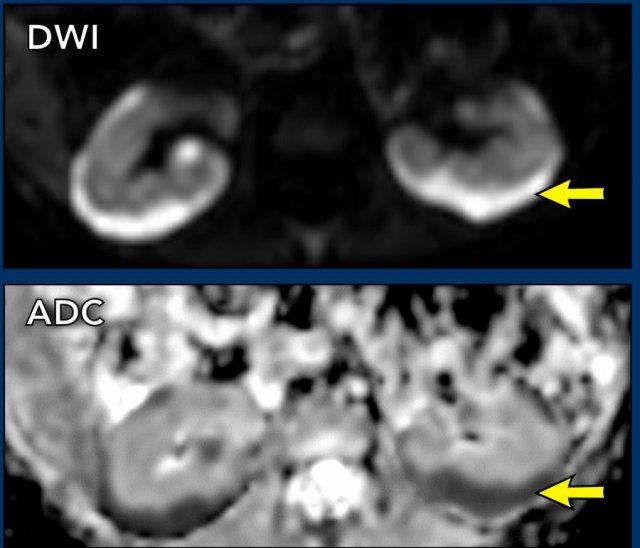

Video

Bé trai 10 tháng tuổi nhập viện vì khối u vùng bụng. Siêu âm ghi nhận khối u ở thận phải. Tổn thương được thể hiện rõ hơn trên MRI. Phần thận còn lại có hệ thống đài bể thận giãn.

Trên hình ảnh ADC, ghi nhận hạn chế khuếch tán không đáng kể.

Kết quả giải phẫu bệnh xác nhận sarcôm tế bào sáng của thận.

Khối u ban đầu được nghĩ đến là u Wilms do mức độ hạn chế khuếch tán không đáng kể, tuy nhiên kết quả giải phẫu bệnh xác nhận đây là sarcôm tế bào sáng của thận.